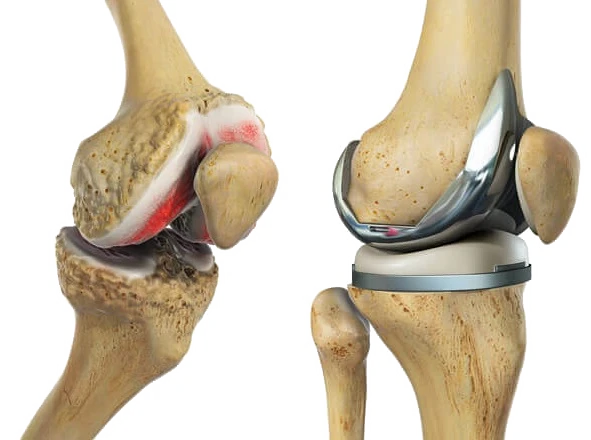

Revalidatie na knieprothese

Een totale of gedeeltelijke knieprothese is een ingrijpende operatie. Een goede revalidatie is essentieel om mobiliteit, kracht en vertrouwen in bewegen opnieuw op te bouwen. Vroeg en doelgericht starten met revalidatie legt de basis voor een vlot herstel in de weken en maanden nadien.